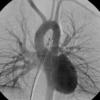

PA angio

Fig 1

Date: 03/23/2004

Views: 3657